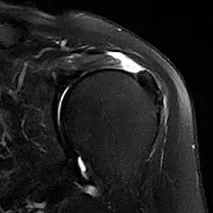

診断は実際の症状やレントゲン、超音波、MRIといった画像診断を用いて総合的に行います。